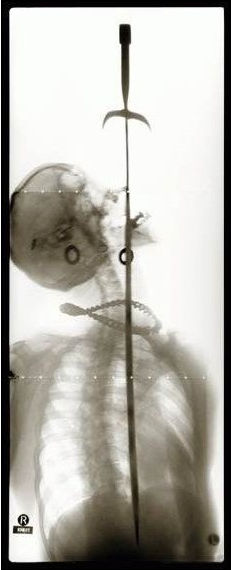

そして、横から見たとき↓

sword_x2.jpg

剣の形がくっきりしています。